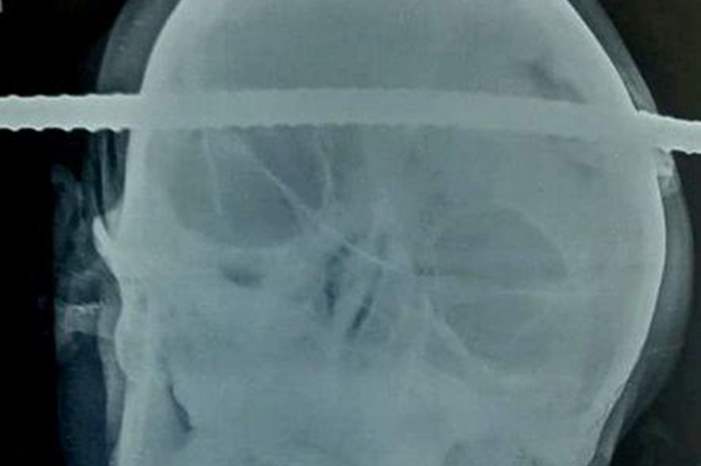

نجا عامل هندي من الموت بأعجوبة، عقب اختراق سيخ حديدي لرأسه، أثناء عمله في موقع بناء وسط الهند.

ووفقا لصحيفة "ديلي ميرور"، سقط سانجاي باهي، البالغ من العمر 21 عاما، أثناء بنائه بئرا ملكا له، متعرضا لاختراق سيخ حديدي لجمجمته، من الجانب الأيمن للأيسر.

ونقل باهي للمستشفى للخضوع لجراحة طارئة، ظل في كامل وعيه طيلة وقتها والتي استمرت 90 دقيقة.

وأضاف الجراح أن السيخ المعدني كان بعيدا ببعض الميلليمترات، عن الأوعية الدموية الرئيسية داخل المخ، المسؤولة عن نقل المعلومات بين الدماغ وأجزاء الجسم.

وتمت الجراحة بنجاح، وما يزال باهي تحت المراقبة الطبية للتأكد من أن الصدأ لم يسبب له أي أضرار.